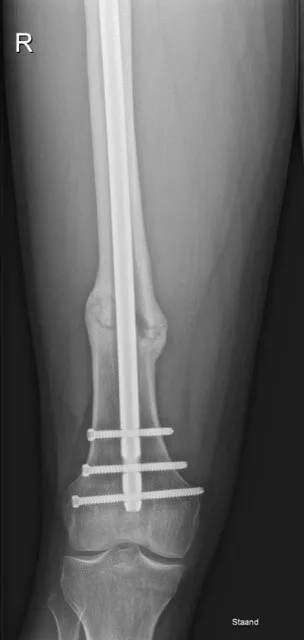

3. Beeldvorming: Een röntgenfoto van het femur (bovenbeen) bevestigt de diagnose dijbeenbreuk. Op de foto ziet men de fractuurlijn, het type breuk (dwars, schuin, spiraalvormig) en hoeveel fragmenten er zijn. Ook is zichtbaar of de botstukken verplaatst zijn. Soms maakt men aanvullend een CT-scan van het been, vooral bij complexe, verbrijzelde breuken, om de fragmenten 3D in kaart te brengen voor de operatieplanning. Bij hoogenergetisch trauma zal men tevens het hele lichaam scannen (trauma CT-scan) om andere letsels niet te missen.

Stap 2: Operatie – intramedullaire fixatie (femurnagel): De standaardbehandeling voor een dijbeenschachtbreuk bij volwassenen is het operatief vastzetten van de botdelen met een intramedullaire nagel. Onder verdoving plaatst de orthopedisch chirurg of traumachirurg een metalen nagel in het mergkanaal van het dijbeen. Via een sneetje bij de heup wordt de pen in het been ingebracht en door het gebroken deel geleid, zodat de botstukken weer uitgelijnd aan elkaar komen te zitten. De pen wordt boven- en onderaan met schroeven vergrendeld, zodat de nagel niet kan bewegen. Dit is een stevige constructie die het gewicht weer kan dragen terwijl het bot geneest. In sommige situaties (bijvoorbeeld bij een fractuur vlak bij de knie of bij bepaalde breuktypes) kan, in plaats van een nagel, een plaat met schroeven aan de buitenkant van het bot worden aangebracht om de breuk te fixeren.